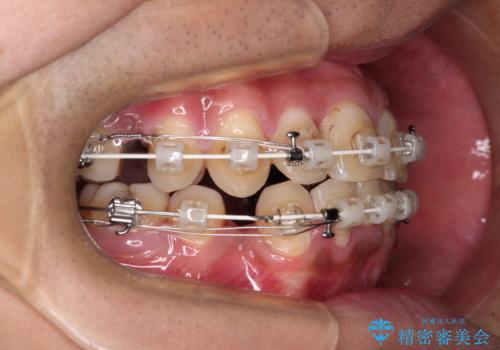

重なって磨きにくい上下の前歯 ワイヤー装置での抜歯矯正

- 前歯のデコボコを改善したいと来院された患者様です。

口元の突出感はないものの、上顎前歯のデコボコが著しかったため、上下顎左右小臼歯4本を抜歯することとしました。

上下の正中位置を改善するため、右下は第一小臼歯を、その他は第二小臼歯を抜歯することとしました。